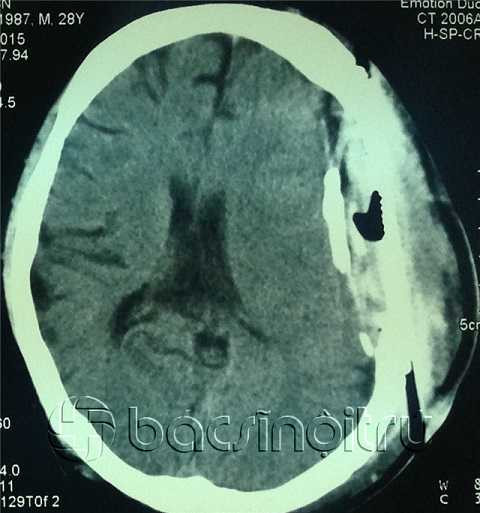

![]() |

| Hình ảnh CT sọ não cho thấy có ổ giảm tỷ trọng không đồng đều ngay dưới da đầu vùng tổn thương |